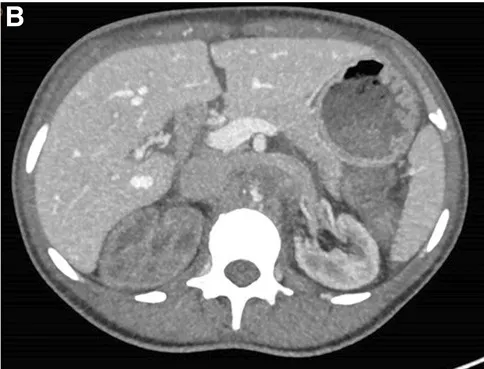

Paciente com dor lombar evoluindo com IRA e anúria